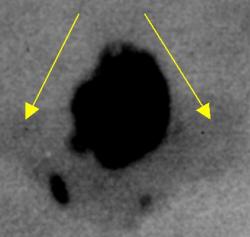

Протокол исследования. Общий фон инволютивно измененной молочной железы (в годы климакса). В правой молочной железе в передних отделах, в верхнем наружном квадранте определяется «узловое образование» значительной интенсивности, однородной структуры (1), неправильно округлой формы, с неровными, местами волнистыми контурами. В окружающей ткани определяются несколько различных размеров очаговых теней значительной плотности. Описанные тени располагаются на фоне локального снижения прозрачности молочной железы (стрелки) – по всей видимости - участок нежного склероза (1 – прямая проекция, 2 – боковая проекция). 3, 4, 5 – патологический участок железы выделен «навигатором», проведена цифровая обработка изображения – тень неоднородной структуры с преимущественным обызвествлением по периферии и известковыми включениями в центре.

Заключение: Инволютивная молочная железы в годы климакса. Фиброаденома (обызвествленная) правой молочной железы с более мелкими обызвествленными фиброаденомами вокруг.